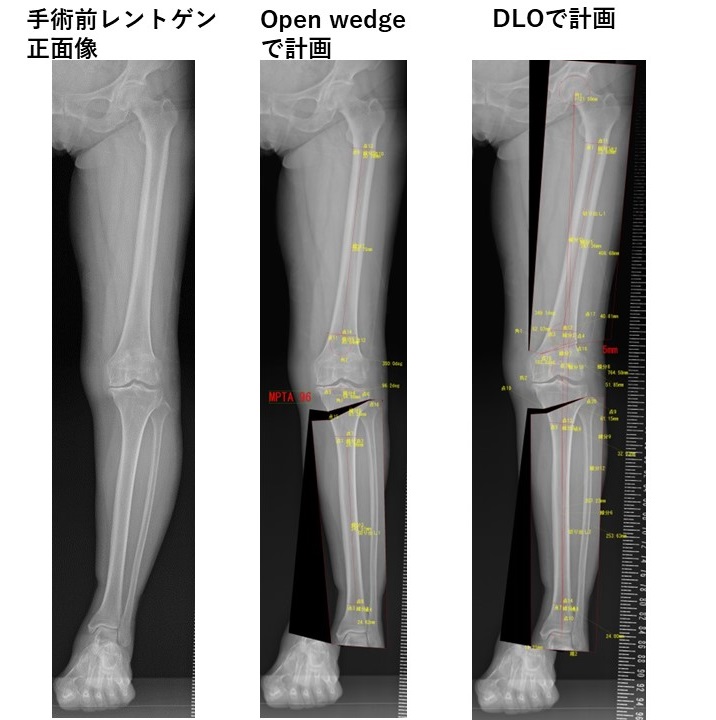

DLO (Double level osteotomy) 手術前後のレントゲン像

手術前のレントゲンで近位脛骨内側角(MPTA)が95°を超えないように計画をたてます。術前計画でOpen wedge 高位脛骨骨切り術のみだと、手術後の近位脛骨内側角(MPTA)が95°をこえることがわかります。術前計画でDLOだと、手術後の近位脛骨内側角(MPTA)が95°以下となることががわかります。

DLO (Double level osteotomy) 手術を行いました。DLO後、下肢全長レントゲン正面・側面像です。目標通り正常よりややX脚、正面像で関節面は地面に平行になりました。